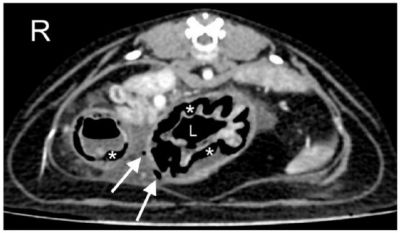

Un scanner est donc réalisé sous anesthésie. L'examen thoracique est normal. Mais l'examen abdominal confirme la péritonite, l'ulcération gastrique, la pneumatose de l'estomac et le pneumo-abdomen (voir cliché en illustration) ainsi qu'une atteinte du pancréas (œdème ou pancréatite).

Le traitement d'une pneumatose gastrique est médical ou chirurgical, selon l'étiologie primaire et la gravité. Ici, une perforation et/ou une nécrose de la paroi stomacale sont suspectées. Une laparotomie exploratrice est donc menée. Elle montre des lésions ulcéreuses marquées de l'estomac, mais toutefois sans perforation. Une gastrectomie partielle est réalisée, et le chat est rendu à ses propriétaires après quelques jours d'hospitalisation.